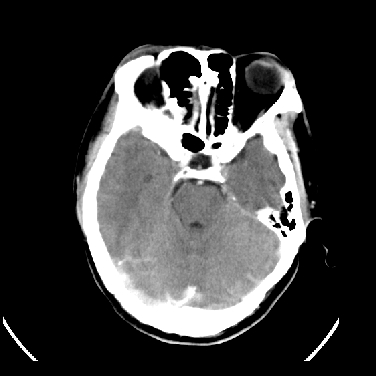

男,45岁,左侧肢体乏力1周。ex:胸片示:两肺团块状、斑片状密度增高影,其内可见小空洞。支纤镜、经皮肺穿示:干酪样物。

结合病史考虑结核性脑炎脑膜炎,伴脑脓肿形成

考虑右侧顶叶脑脓肿形成。

同意“考虑结核性脑炎脑膜炎,伴脑脓肿形成”的意见,不轻易怀疑肿瘤。

考虑结核性脑炎脑膜炎,伴脑脓肿形成。

考虑右侧顶叶脑脓肿(结核性?)。

结核性脑脓肿可能大

结合病史考虑结核性脑炎脑膜炎,伴脑脓肿形成,囊变转移瘤不除外